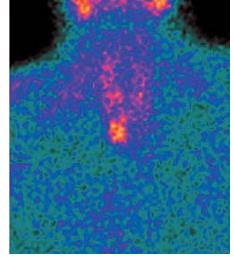

Иллюстрации и схемы по остеопорозу и паращитовидной железе

Раздел: Картинки жизни